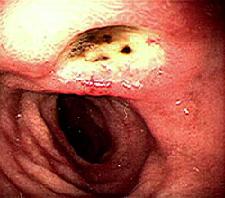

Диагностировать язву двенадцатиперстной кишки можно благодаря эндоскопии: этот метод дает врачу полную информацию о состоянии больного. При обнаружении язвы оценивает ее расположение, размеры, тип, наличие рубцов. Во время процедуры производится забор образца слизистой по краю дефекта для исследования на присутствие хеликобактерий.